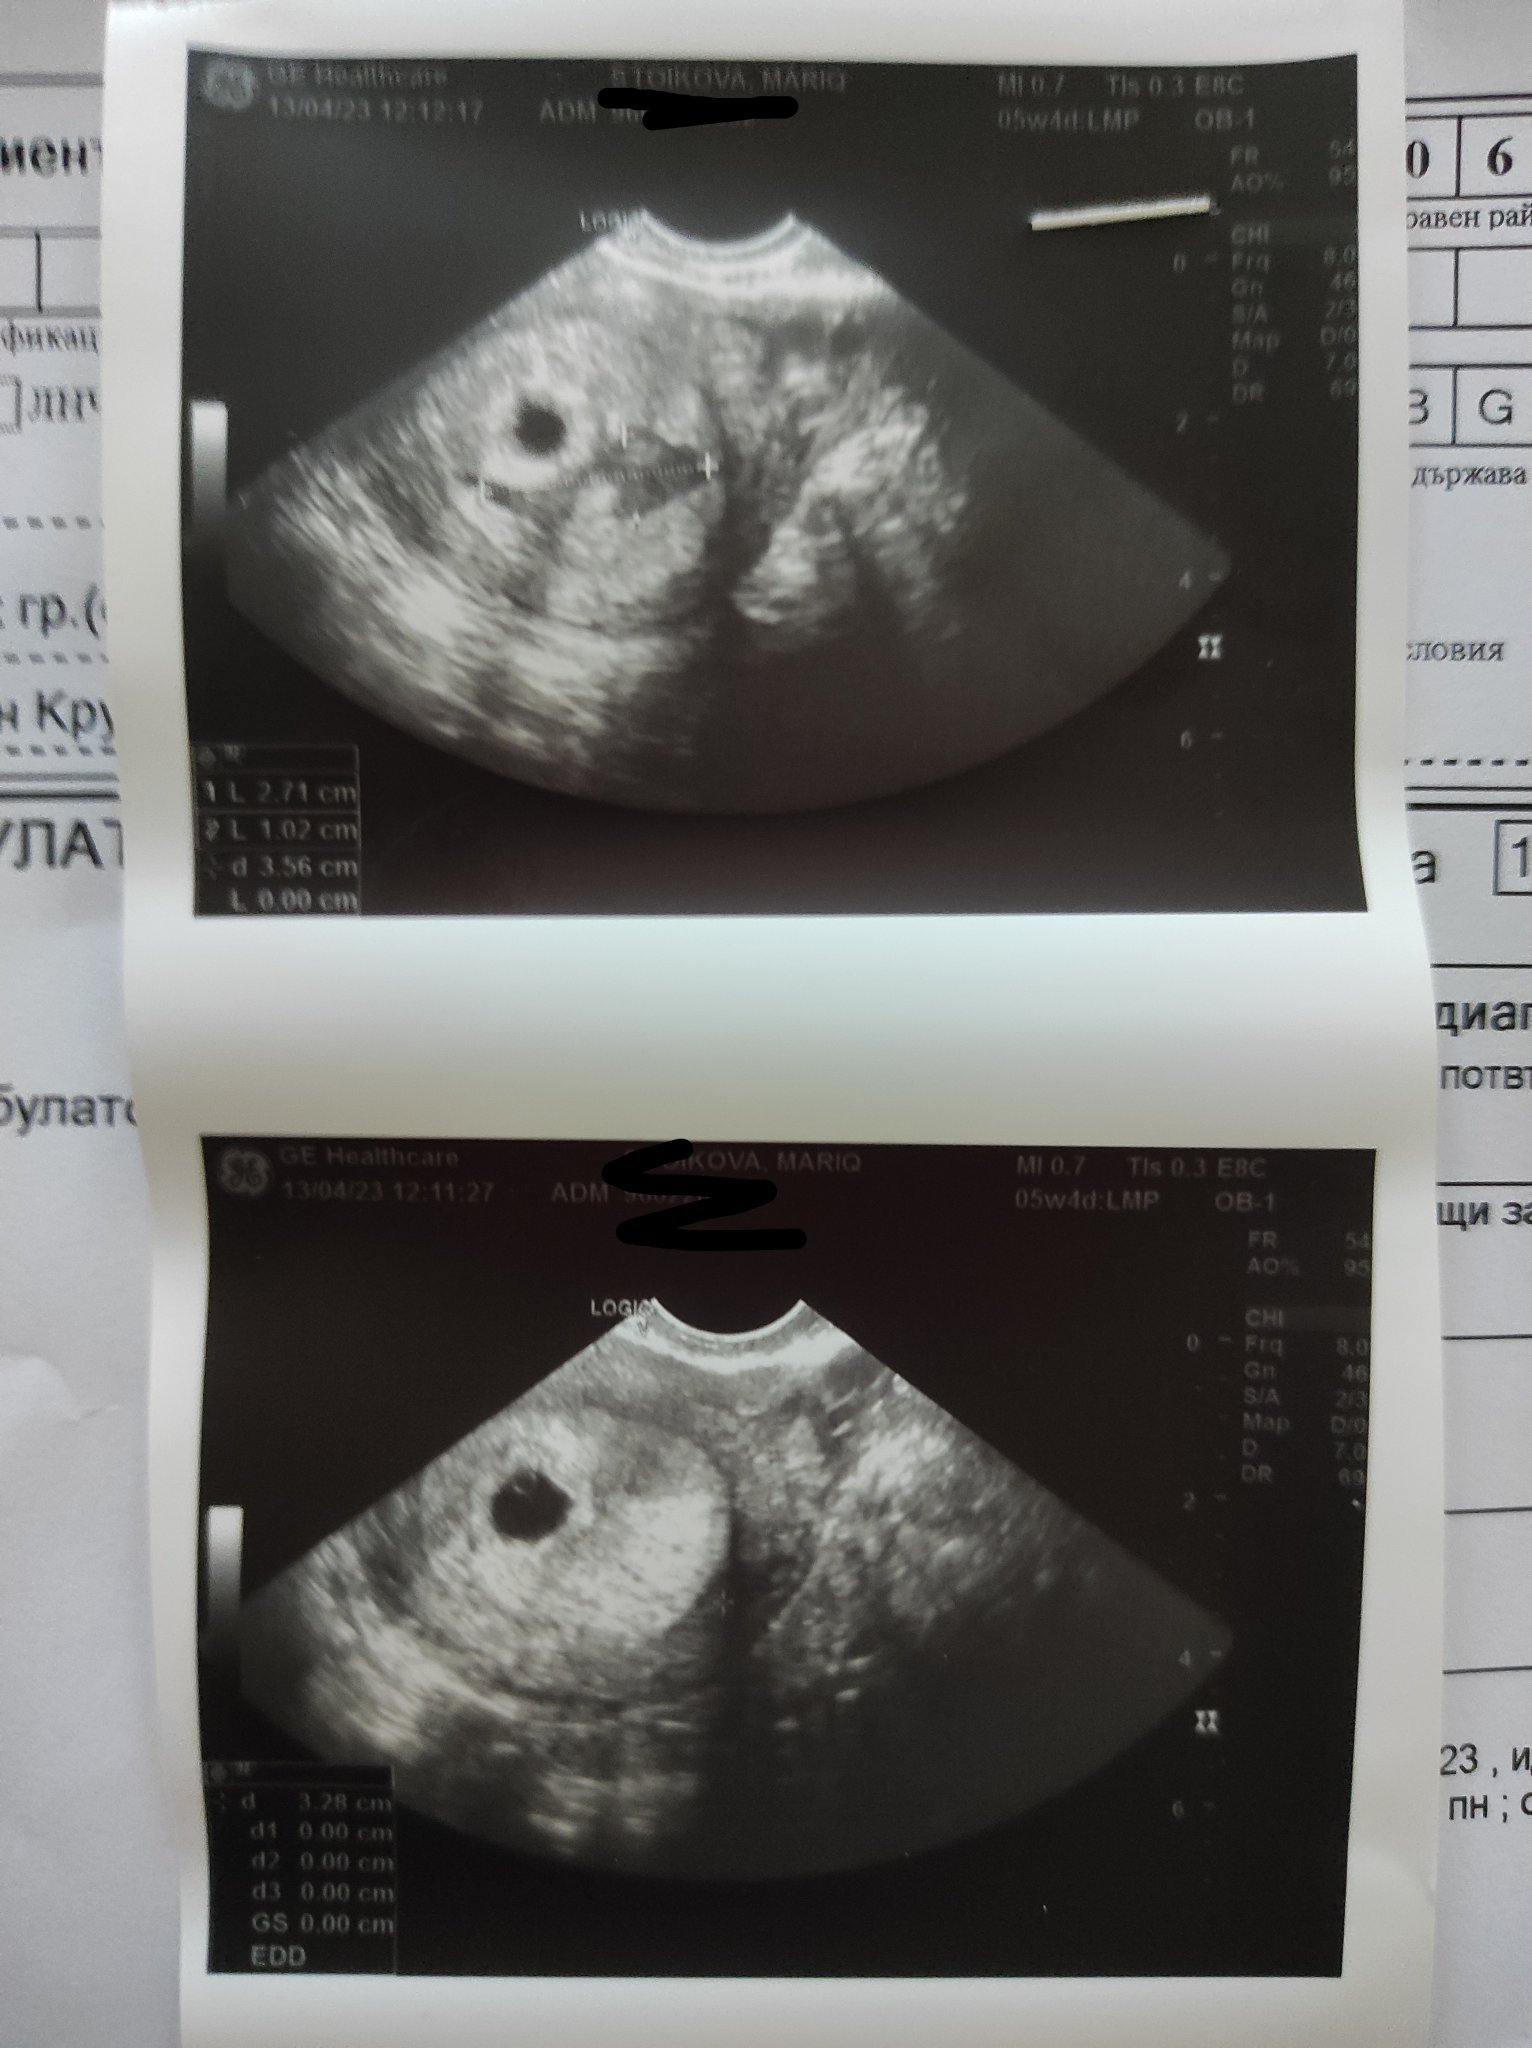

Ето я и нашата точка , днес бях на преглед. 5 седмици и 4 дни , вътрематочна бременност , много добре оформен сак , ноо има отлепяне ,което не е никак малко 😔 ще пия но шпа и дуфастон. Повече почивка , без секс , без вдигане на тежко и претоварване . На 25 съм пак на преглед ,дано всичко да си е наред , да няма кървене и някакви други не желани екстри. Даже на едната снимка се вижда отлепянето, като сянка е

Последна редакция: чт, 13 апр 2023, 14:28 от M a r i a